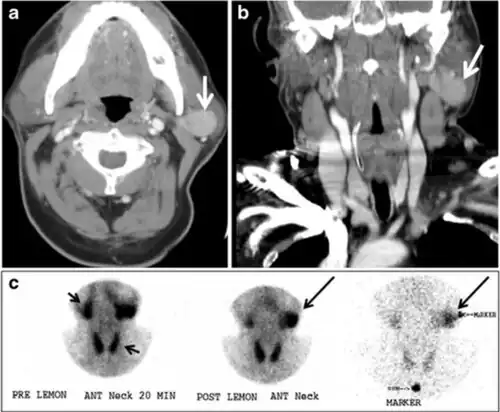

Parathyroid adenoma (PA) is the most common cause of primary hyperparathyroidism. Ectopic parathyroid adenoma is rare. The third and fourth pharyngeal pouches represent the embryological origin of the parathyroid tissues, and ectopic parathyroid adenoma can ultimately develop anywhere along their migration course. In a large retrospective study of patients with primary hyperparathyroidism, PA was detected in the intra-thyroid location in 0.7% of cases. In another retrospective analysis of 202 patients with ectopic PA, the intra-thyroidal location was found in 18% of the cases. Intra-thyroid parathyroid adenomas mimic thyroid nodules in CT scans and may even show uptake on a thyroid iodine scan. Correlation with laboratory workup, including measurement of serum parathyroid hormone and calcium level, is required. In addition, the evaluating radiologist should search for radiological manifestations of hyperparathyroidism, such as osteopenia, bone resorption, and brown tumours (Fig. 22).[1]

Fig. 22. A 26-year-old male patient with elevated serum parathyroid hormones and calcium secondary to intra-thyroid parathyroid adenoma. a, b Enhanced axial and coronal CT scan of the neck demonstrate a well-defined hypodense right thyroid nodule (white arrows). c Bone window coronal CT scan shows lytic expansile lesions at the right mandible and left frontal bone (white arrows). d Transverse colour Doppler ultrasound of the neck demonstrates a well-defined, heterogonous, predominantly hypoechoic right thyroid nodule measuring 2.7 cm, with mild increased vascularity and no internal micro-calcifications (white arrow). e, f Delayed anterior planar and fused SPECT/CT parathyroid Sestamibi scan at 2 hours demonstrate persistent focal activity in the right thyroid lobe (white arrows). Note the scattered mandibular/maxillary uptakes in planar image representing the known brown tumours.[1]

In the case of inconclusive Tc99m Sestamibi and neck US imaging, FNA biopsy with FNA-iPTH (intact parathyroid hormone) measurement can provide simultaneous biochemical and cytological evidence. Elevated FNA-iPTH measurement, as compared to serum iPTH, is considered positive and diagnostic of parathyroid adenoma.[1]